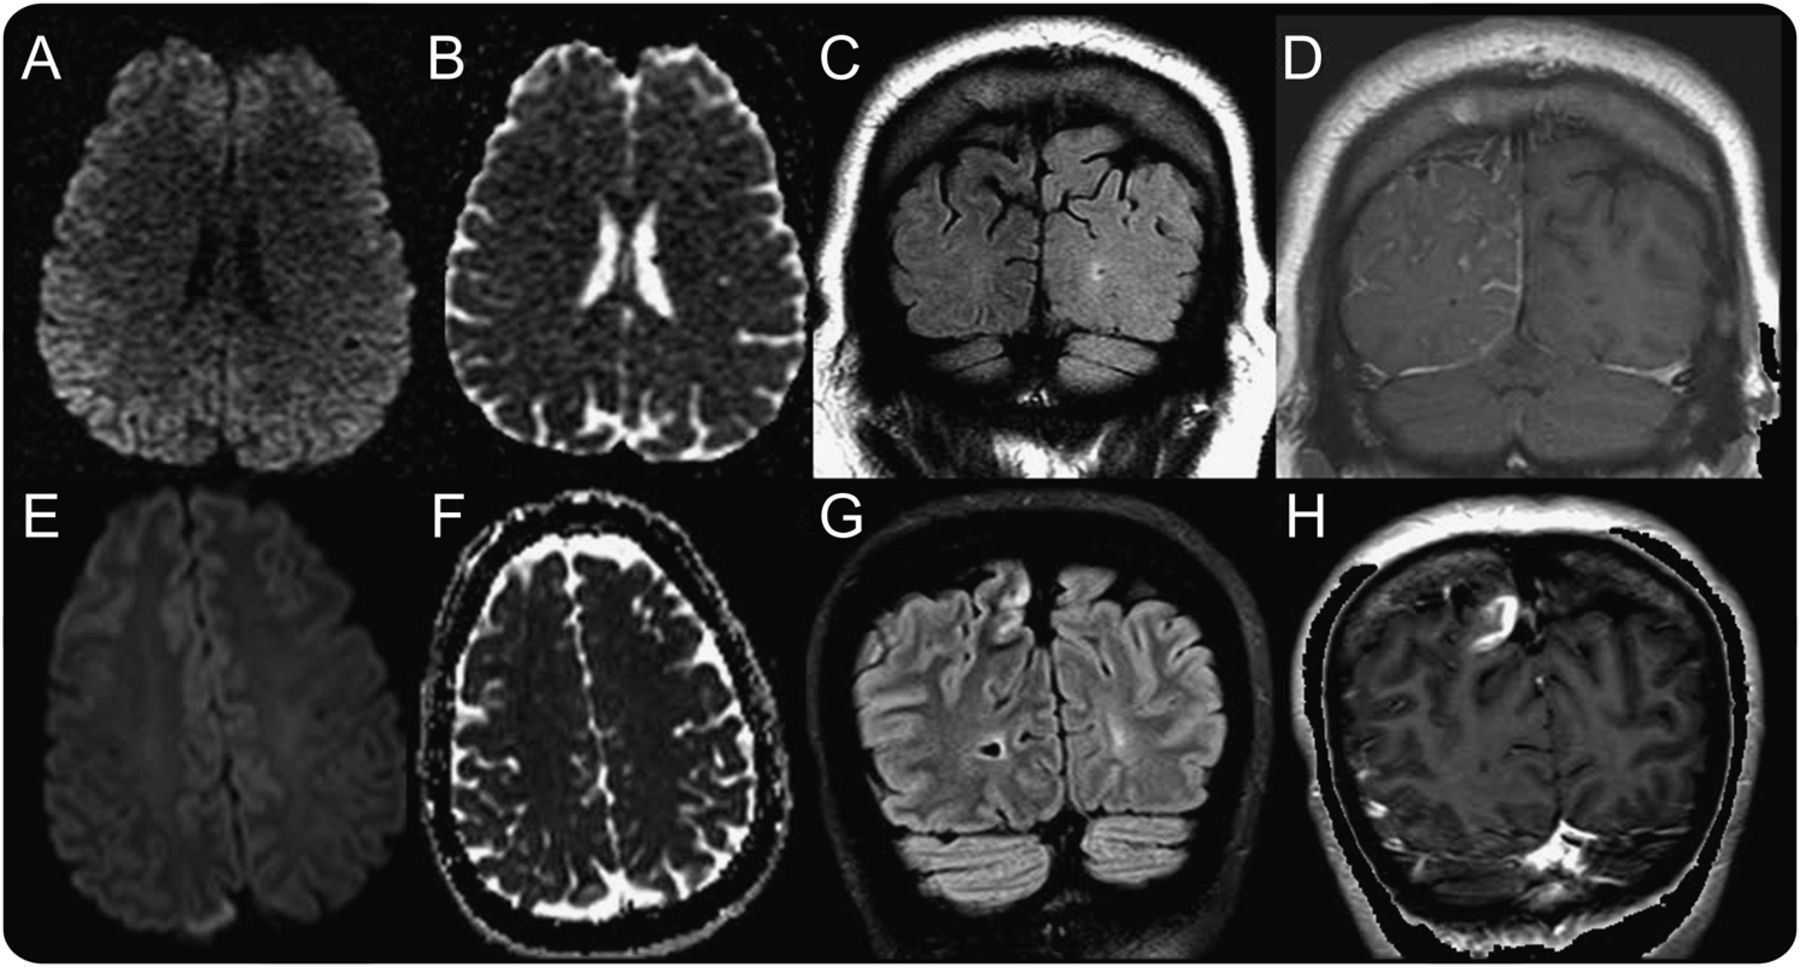

头部CT排除颅内出血。实验室调查排除白细胞增多,肾或肝功能异常,电解质紊乱,除了血糖升高到541 mg / dL(案例1)和306 mg / dL(例2)。大脑皮质增加信号基于MRI显示微妙diffusion-weighted序列没有相应降低表观扩散系数序列信号(图1中,A和B)。叠加震源,软膜的(例1),或者皮质(例2)钆增强观察、与相邻的皮层下hypointensity t2加权成像(T2WI)和fluid-attenuated反转恢复序列(天赋)(图1、C、D、G和H)。

核磁共振大脑有和没有对比为例1(模拟)和2 (E-F)。轴向diffusion-weighted序列(A, E)显示微妙的右枕叶和顶叶增加信号与相应的增加信号情况下的表观扩散系数2 (F)。日冕fluid-attenuated反转恢复(C、G)演示了皮层下hypointensity。冠状t1 gadolinium-enhanced图像(D, H)演示gyriform软膜的增强在案例1 (D)和焦皮质增强2 (H)。